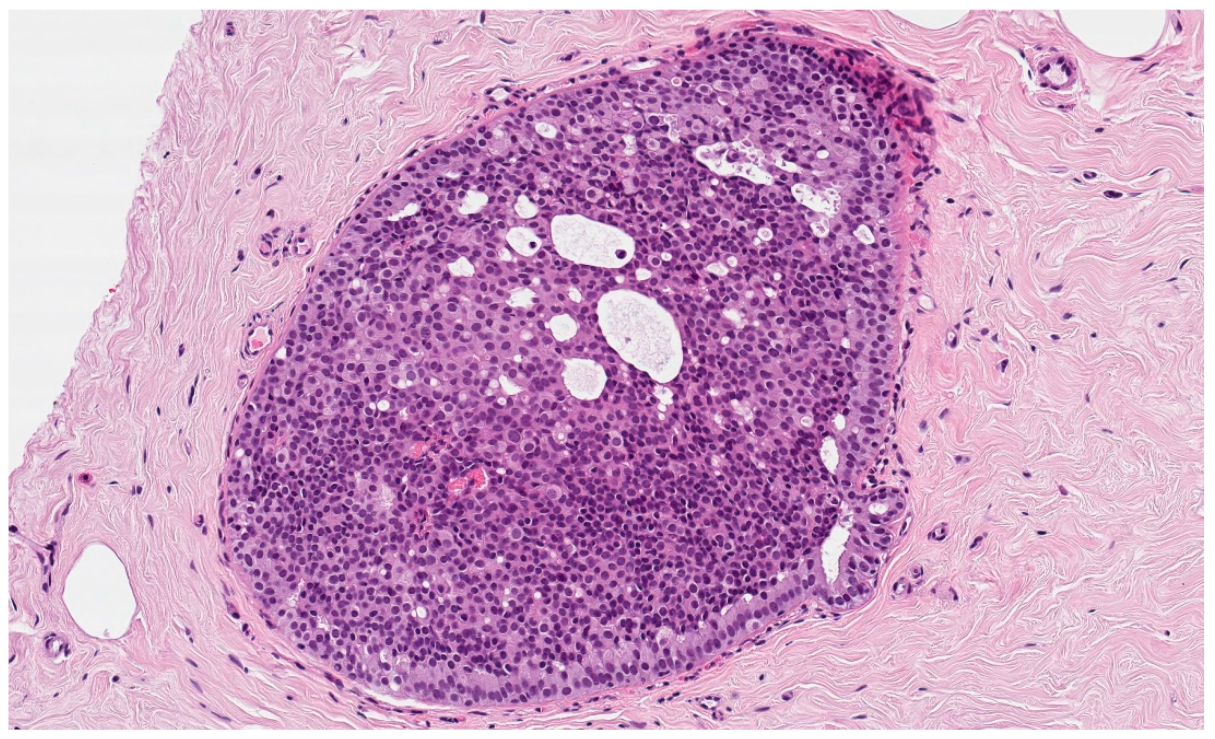

We investigated a potential correlation between patient’s age, lesion size, diameter of the needle (with an equal number of biopsy samples, more tissue is collected with a larger needle), number of cores, complete macroscopic removal of the lesion, cases showing low-grade DCIS only in cores with microcalcifications, and the chance of upgrade to a worst grade DCIS or invasive ductal carcinoma (IDC). Since the BIRADS is often very subjective [18], we have excluded it from the analysis. Figure 2 represents a low-grade DCIS.

Figure 2.

Histological features of low-grade DCIS from a breast biopsy showing bland homogeneous cells contained within the duct, forming rigid cell ‘bridges’ across the duct space in a cribriform architecture. In this case, the abnormal duct is surrounded by fibrotic stroma (hematoxylin and eosin, original magnification 100×).